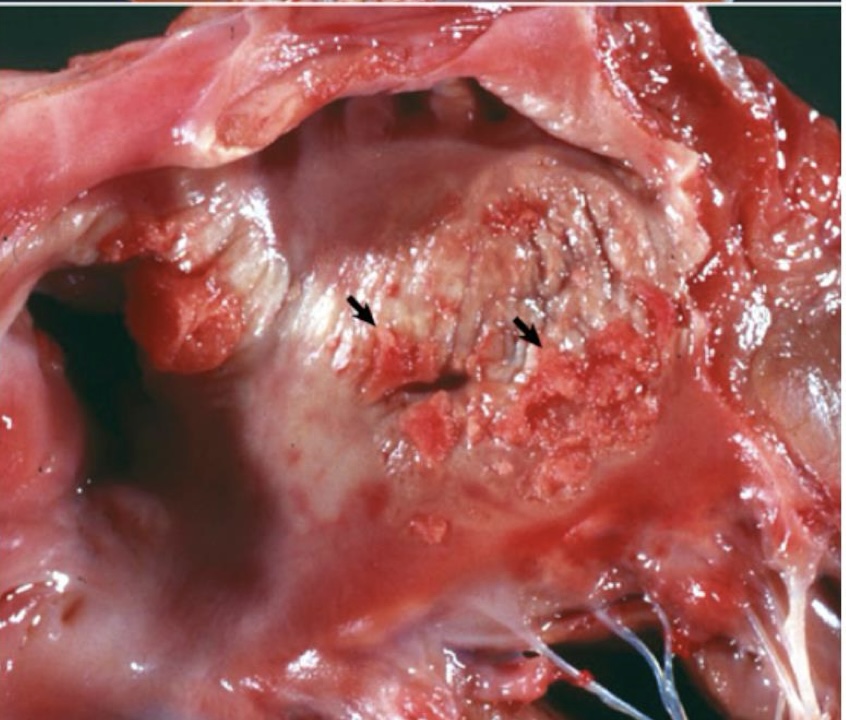

what is this showing?

ulcerative endocarditis → whitish-yellow areas of endocardial mineralization forming plaques that extend to the leaflets